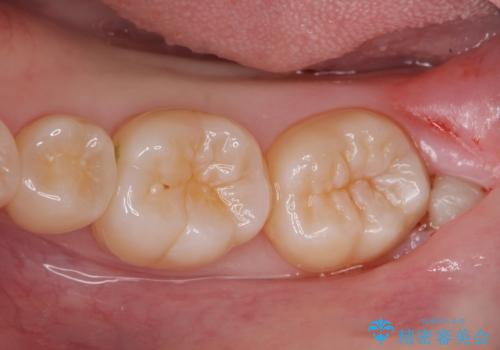

左の親知らず抜歯したい。

- 左上下親知らず抜きたいとの事で来院。

無事に親知らず抜歯ができました。